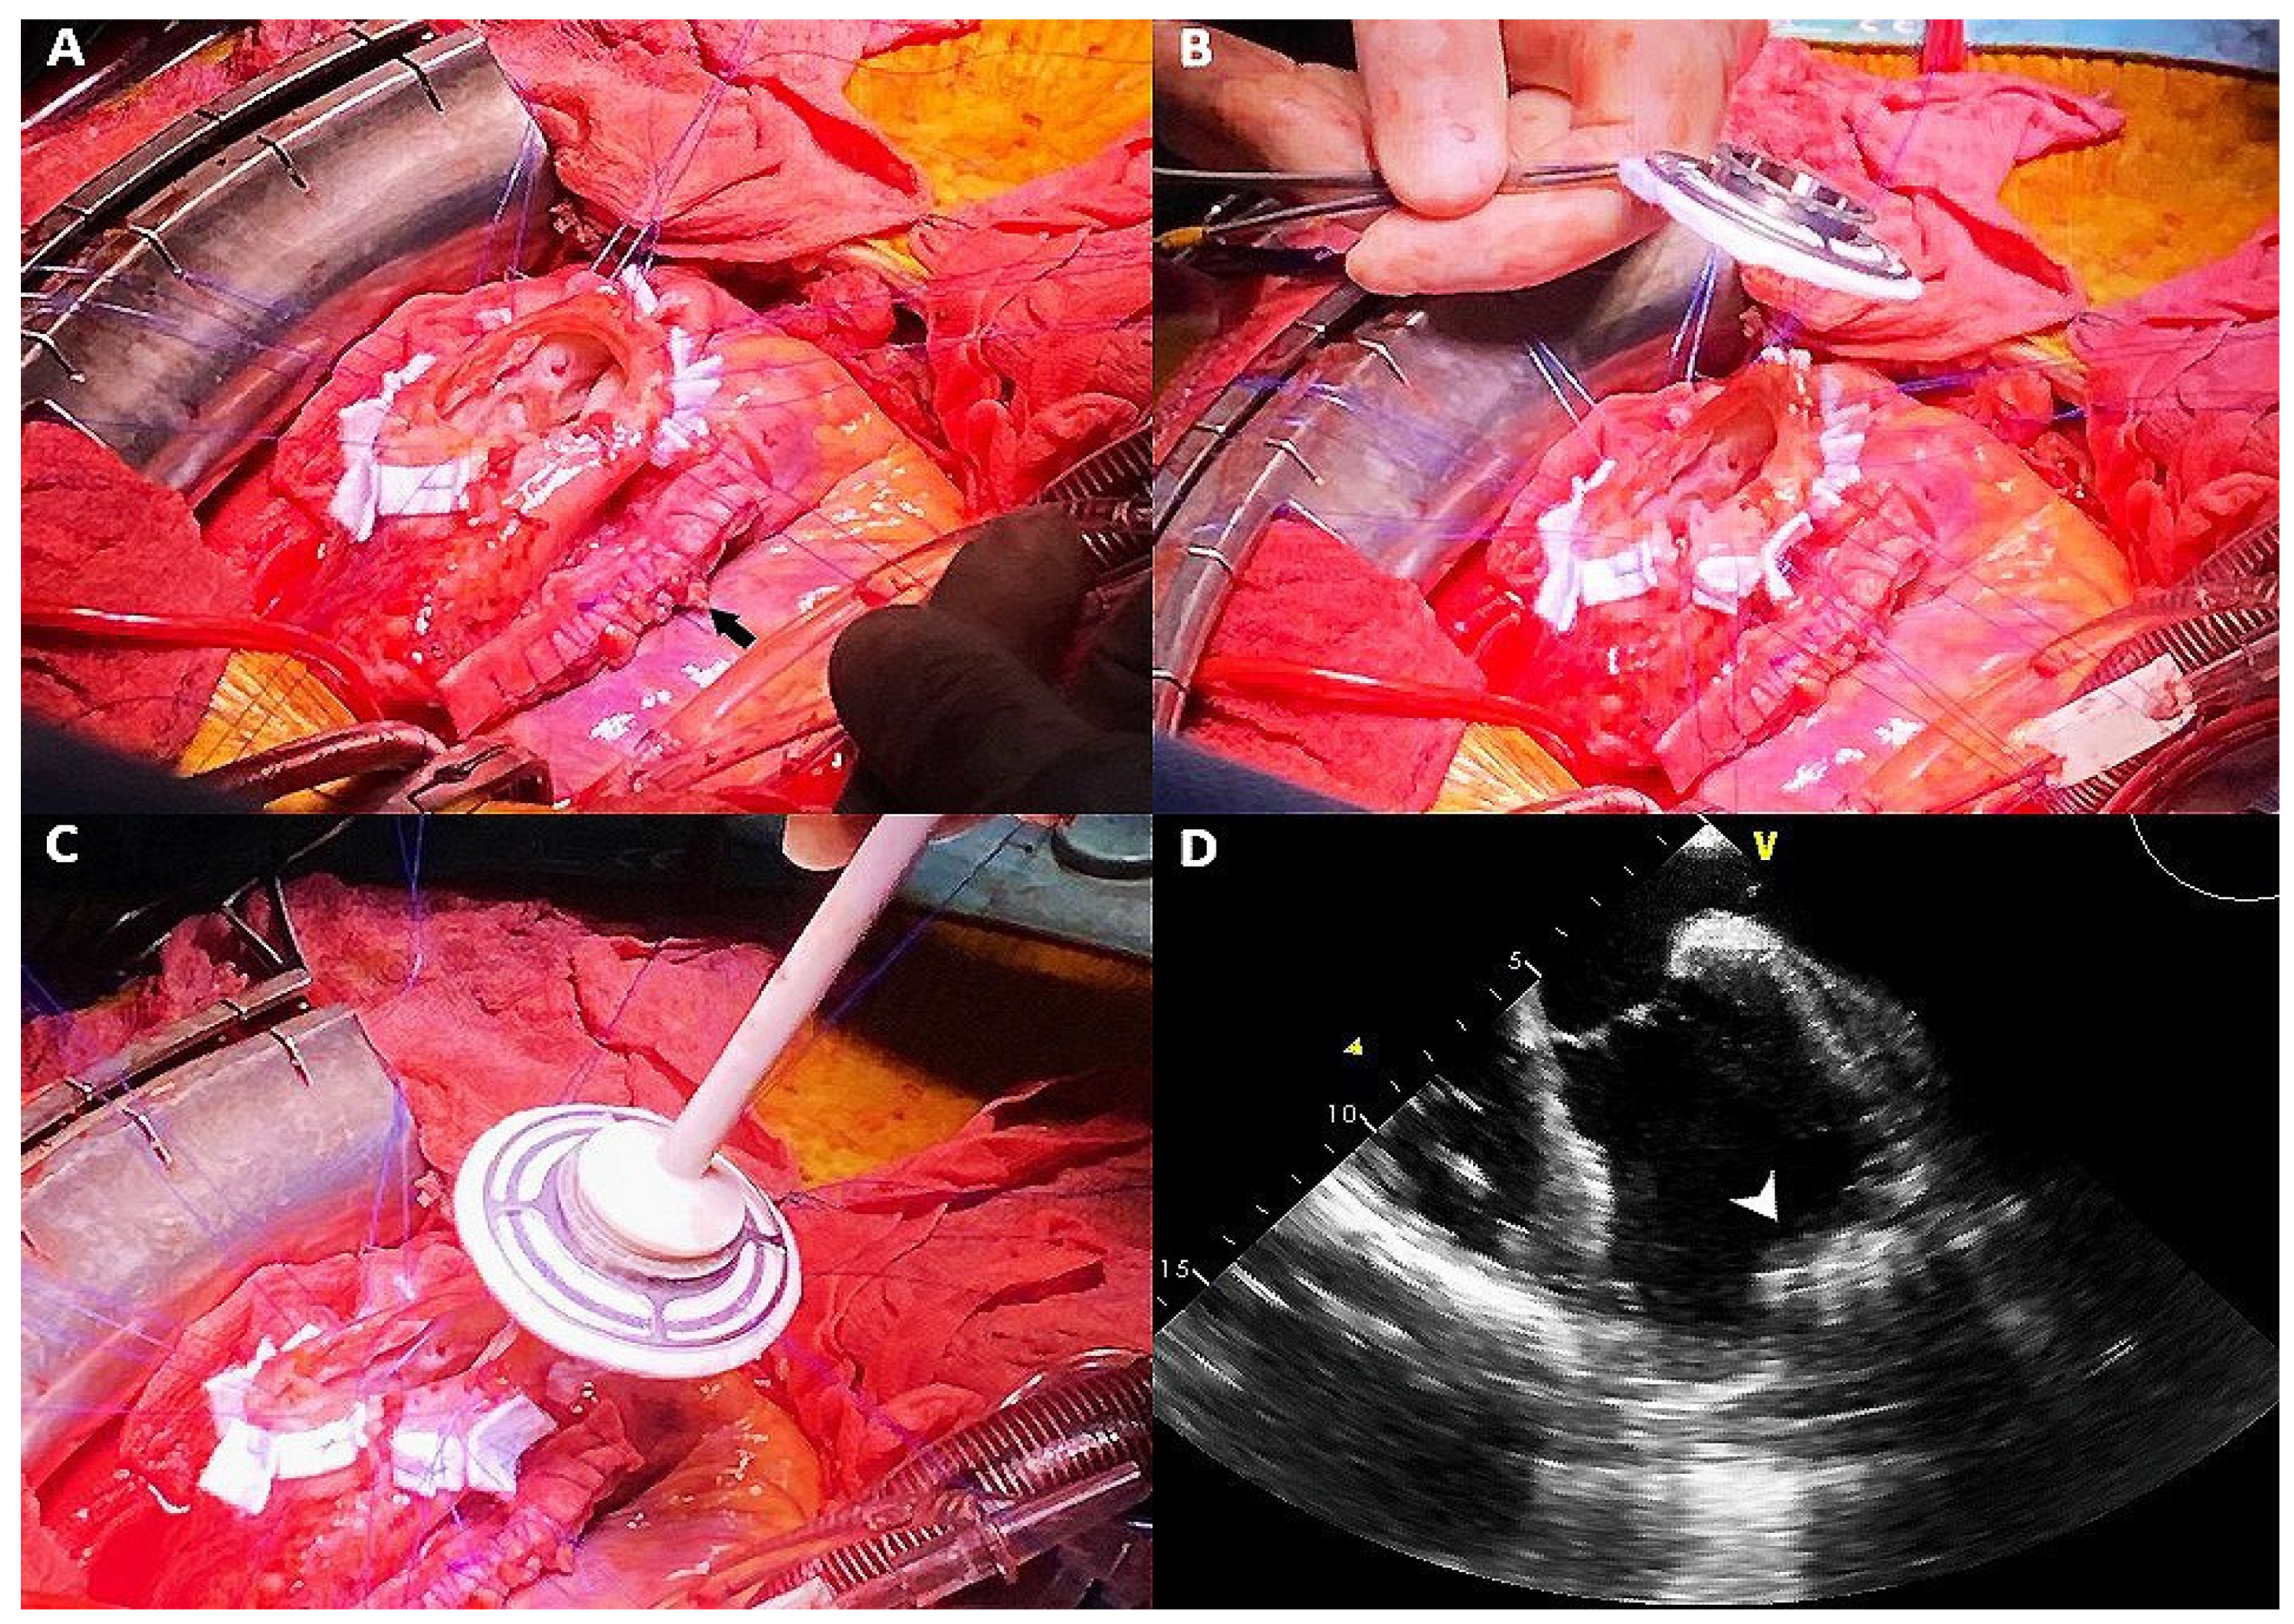

| 18 May 2020 | Heartmate III implantation with and concomitant surgical plication of the anterolateral wall pseudoaneurysm |